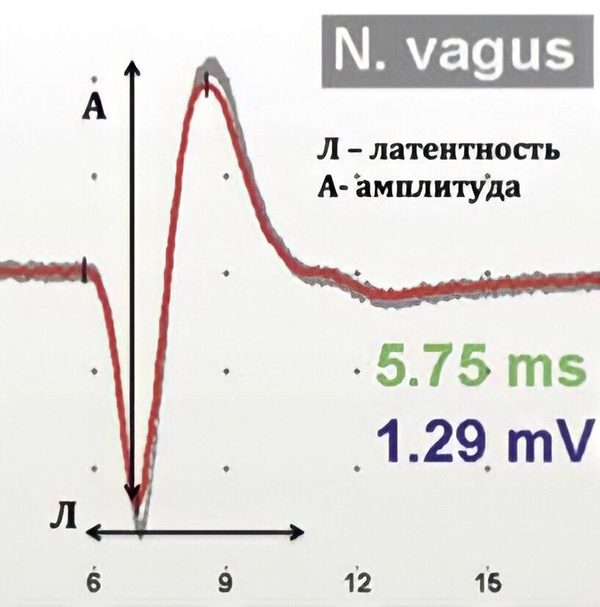

Начиная с 90-х годов XX века хирурги, оперирующие на щитовидной железе, стали использовать электромиографический контроль функции гортанного нерва. В последние 15 лет интраоперационный нейромониторинг претерпел ряд значительных изменений, в первую очередь связанных с внедрением неинвазивных методов регистрации сигнала с голосовых складок. Появилась возможность контроля и записи на цифровые носители таких нейрофизиологических параметров гортанных нервов, как амплитуда и латентность, и самое главное — хирург в ходе операции может оценить сохранность гортанного нерва, спрогнозировать функцию гортани в послеоперационном периоде и тем самым предотвратить двусторонний парез, изменив план операции.

При постоянном мониторинге специальная клипса фиксируется к n. vagus (к блуждающему нерву, ветвью которого является тот самый возвратный гортанный нерв n. recurrens), данные по амплитуде и латентности доступны хирургу в реальном времени ежесекундно, что позволяет моментально отреагировать на нарушения проведения нервного импульса по нерву и предотвратить его повреждение, изменив хирургическую тактику. Это безопасный и надежный метод контроля электрофизиологического состояния гортанных нервов.

Операция видеоэндохирургическая гемитиреоидэктомия с истмусэктомией справа (удаление одной доли щитовидной железы и ее перешейка) у пациента 40 лет с доброкачественным образованием щитовидной железы проводилась эндоскопическим методом: эндоскопическая техника дает несравнимую с открытыми операциями возможность визуализации всех анатомических структур. В начале операции, приблизившись к нервам, мы проверили «замкнутость цепи»: если нерв отвечает на стимуляцию, на мониторе появляется сигнал, по его амплитуде оценивается степень его травматизации, что позволяет внести коррективы в ход хирургического вмешательства. Так определяют наличие или отсутствие проблем, НЕ связанных с данной операцией. На рис. 2 сигнал от возвратного гортанного нерва. Далее в процессе операции, как я уже отмечал выше, можно в любой момент контролировать сохранность функции нерва.

Протокол постоянного мониторинга представлен двумя линиями и демонстрирует ежесекундные данные по величине амплитуды и латентности.